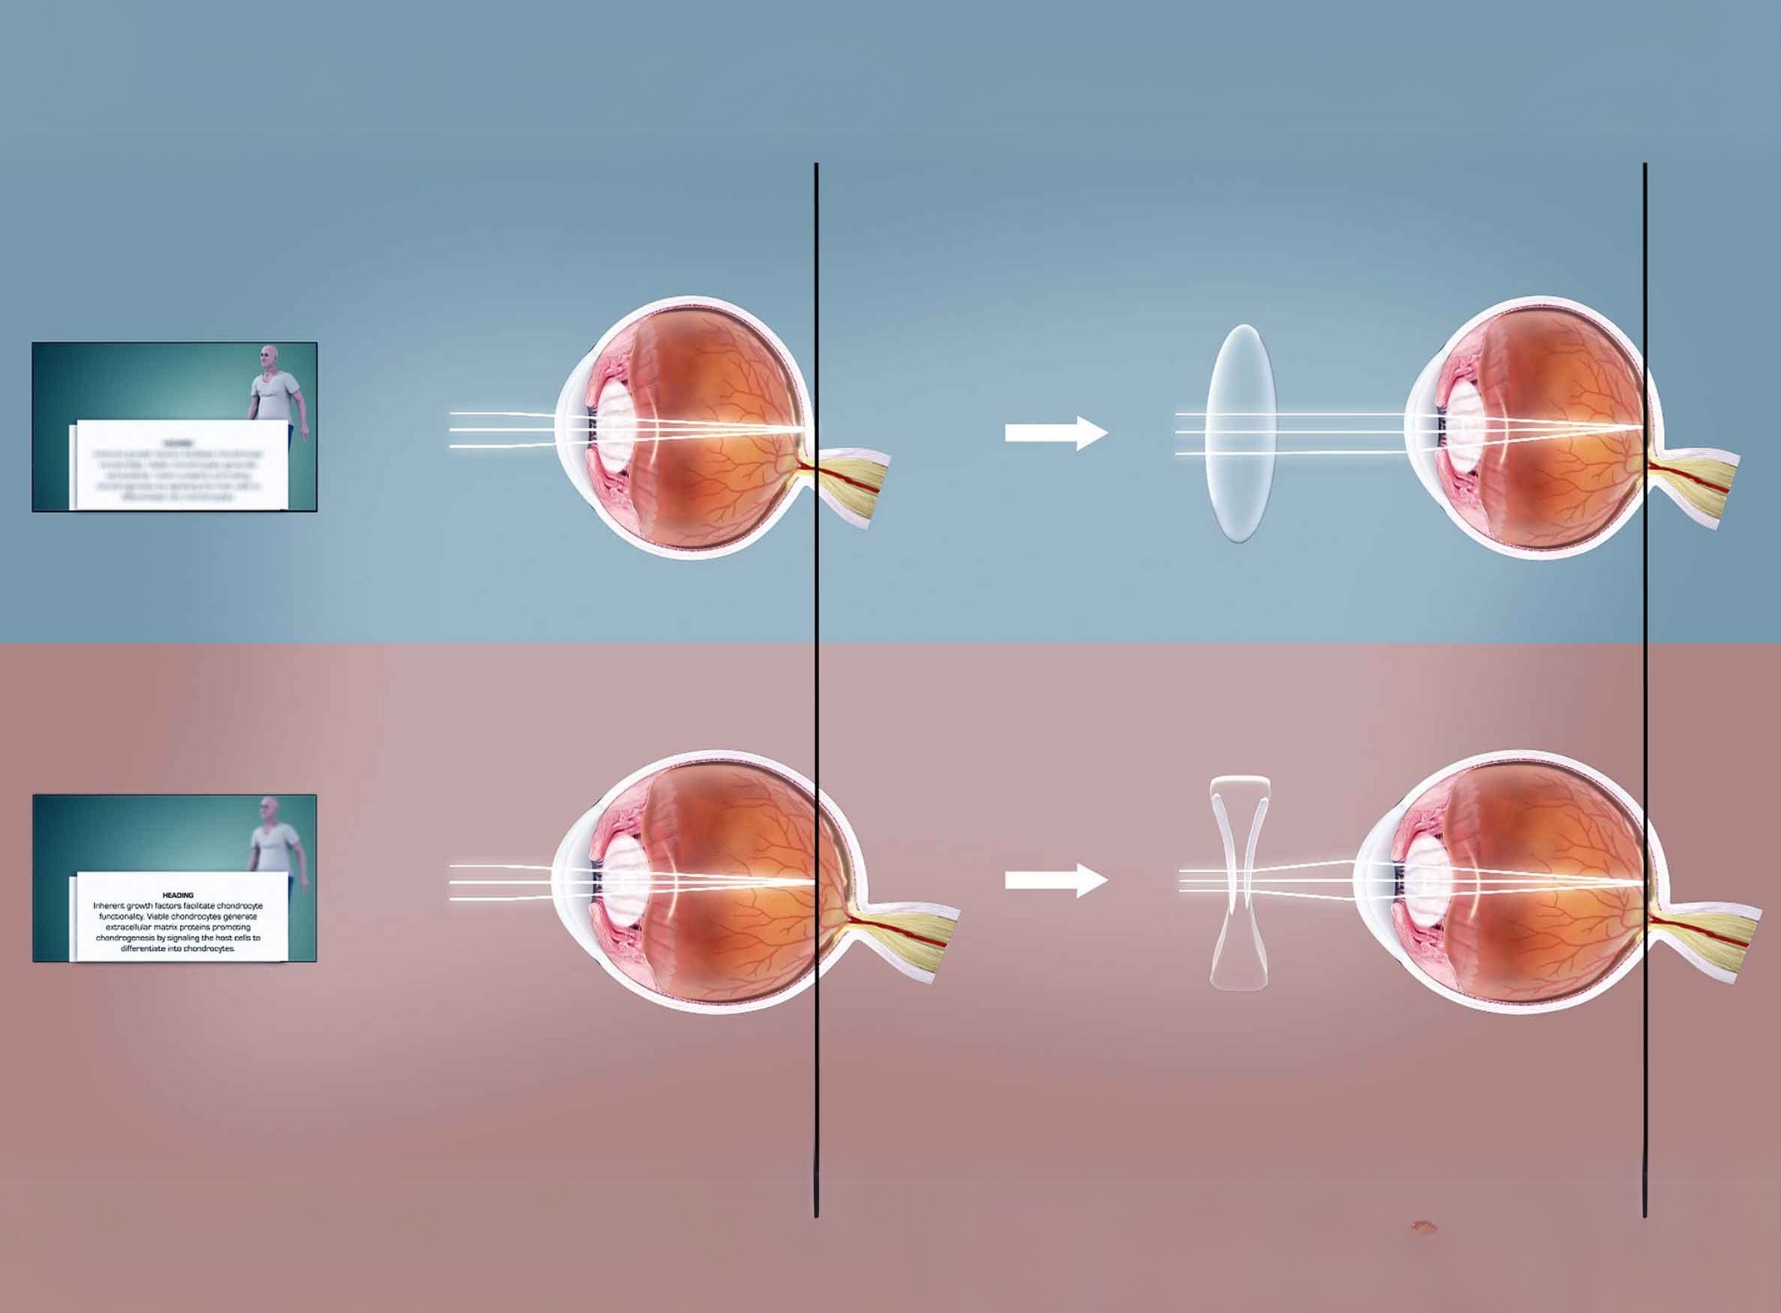

Refractive Error Treatment

Refractive errors such as myopia, hyperopia, astigmatism, and presbyopia affect vision clarity and may require corrective solutions. Our clinic offers advanced diagnostic evaluations to determine the most suitable treatment for each patient. Depending on the condition, we provide prescription eyeglasses, contact lenses, or laser correction procedures like LASIK and Contoura Vision. Patients with high refractive errors can also opt for specialized implantable contact lenses (ICLs) for long-term correction. Our experienced specialists customize treatment plans to ensure optimal vision improvement and patient comfort. Regular follow-ups are conducted to monitor progress and make necessary adjustments for sustained clarity.